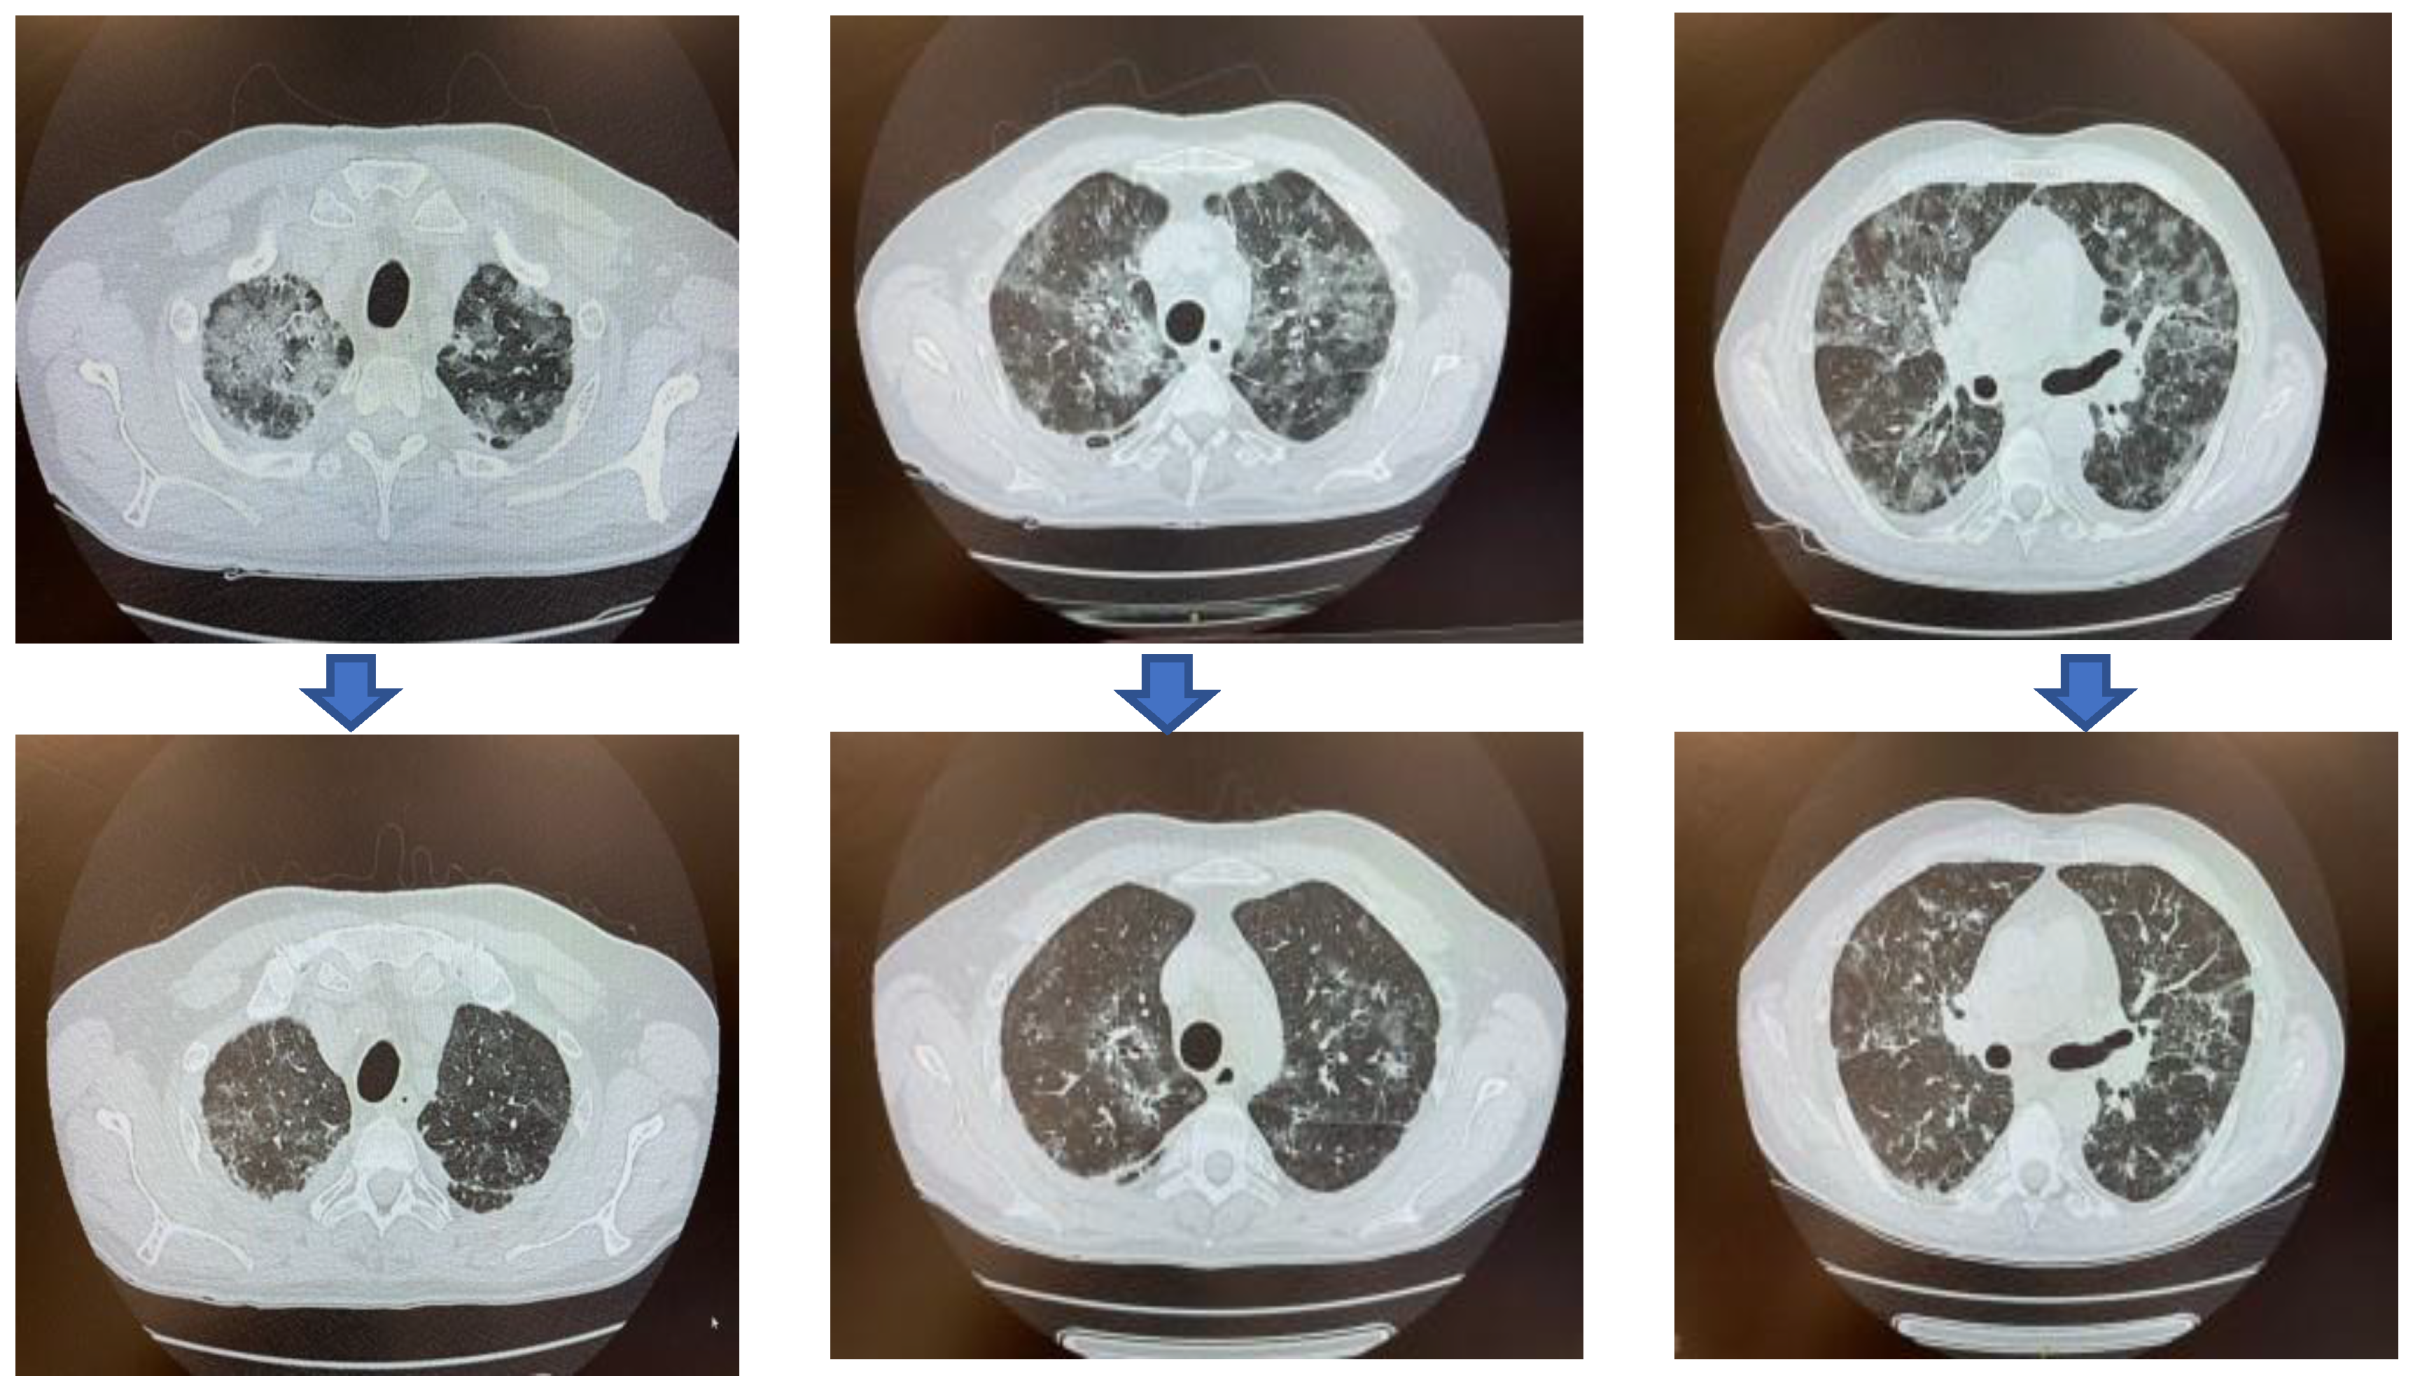

Clinical and Virological Response to Convalescent Plasma in a Chronic Lymphocytic Leukemia Patient with COVID-19 Pneumonia